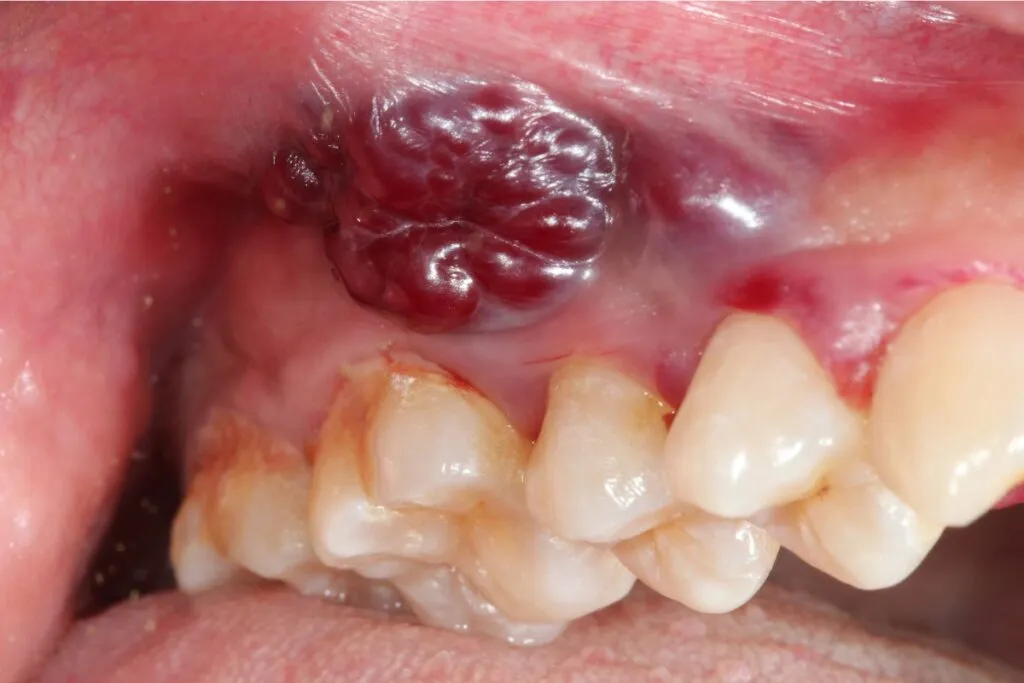

Innym bardzo ważnym sygnałem ostrzegawczym są niegojące się owrzodzenia lub ranki w jamie ustnej, które utrzymują się ponad 2-3 tygodnie i mogą krwawić przy dotyku. W przeciwieństwie do typowych aft czy urazów, które goją się stosunkowo szybko, zmiana nowotworowa jest uporczywa. Może wyglądać jak mała ranka, nadżerka, a czasem nawet jak mały kalafiorowaty twór. Jeśli masz wątpliwości, czy to zwykłe skaleczenie, czy coś poważniejszego, zasada jest prosta: jeśli nie goi się w ciągu dwóch, maksymalnie trzech tygodni, należy to zbadać.

Zmiany na dziąsłach i błonie śluzowej policzków bywają łatwo mylone ze stanem zapalnym, urazami od szczoteczki czy źle dopasowanej protezy. Dlatego tak istotne jest, aby być czujnym na ich uporczywość. Jeśli zauważysz białe lub czerwone plamy, zgrubienia, owrzodzenia na dziąsłach lub wewnętrznej stronie policzków, które nie ustępują po 2-3 tygodniach, mimo ewentualnego leczenia przeciwzapalnego, nie bagatelizuj tego. Konsultacja ze stomatologiem lub laryngologiem jest w takiej sytuacji niezbędna.